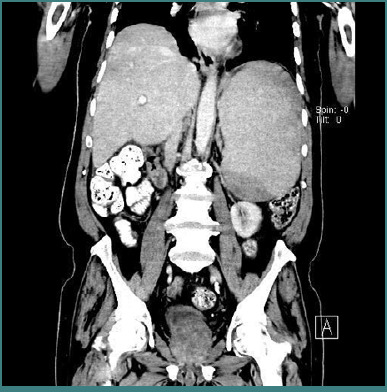

慢性炎症性脱髓鞘性多神经根病(CIDP)是一种获得性免疫介导的神经病变,其特征是进行性或复发缓解的近端和远端虚弱。淋巴瘤是与CIDP相关的多种血液恶性肿瘤之一。脾边缘区淋巴瘤(SMZL)是一种罕见的惰性b细胞非霍奇金淋巴瘤,典型表现为脾肿大和细胞减少。SMZL与CIDP同时发生极为罕见;因此,诊断提出了一个独特的挑战,无论是诊断和治疗。我们报告一位65岁男性病患,表现为进行性近端无力、盗汗及脾肿大。检查显示全血细胞减少,影像学检查证实脾肿大。进一步的检查,如骨髓活检和脾脏组织病理学,分别表明骨髓和SMZL细胞减少。同时,根据临床表现,以及肌电图和神经传导检查,建立CIDP的诊断。对于CIDP,开始免疫抑制治疗;然而,由于其惰性性质,未对SMZL进行治疗。他在接受CIDP治疗后表现出部分神经系统改善。这强调了治疗这两种疾病的重要性。在本病例中提出了罕见的CIDP和SMZL的关联,强调了对神经和血液异常患者进行全面诊断的重要性。因此,对于此类患者的管理,及时识别和适当的治疗方法对于改善结果是必要的。

Chronic inflammatory demyelinating polyradiculopathy (CIDP) is an acquired immune-mediated neuropathy characterized by progressive or relapsing-remitting proximal and distal weakness. Lymphomas are among various hematological malignancies associated with CIDP. Splenic marginal zone lymphoma (SMZL) is a rare, indolent B-cell non-Hodgkin lymphoma that classically presents with splenomegaly and cytopenia. The co-occurrence of SMZL and CIDP is extremely rare; the diagnosis thus presents a unique challenge both diagnostically and therapeutically. We report a 65-year-old male patient with progressive proximal weakness, night sweats, and splenomegaly. Investigations revealed pancytopenia with imaging studies confirming the splenomegaly. Further investigations, such as a bone marrow biopsy and histopathology of the spleen, were indicative of a hypocellular marrow and SMZL, respectively. Simultaneously, a diagnosis of CIDP was established based on clinical findings, as well as electromyography and nerve conduction studies. For CIDP, immunosuppressive therapy was initiated; however, no treatment was administered for SMZL due to its indolent nature. He showed partial neurological improvement with the treatment given for CIDP. This underlines the importance of treating both diseases. The rare association of CIDP and SMZL is presented in this case, highlighting the importance of a comprehensive diagnostic workup in patients with neurological and hematological abnormalities. Therefore, for the management of such patients, timely identification and appropriate therapeutic approaches will be necessary for an improved outcome.